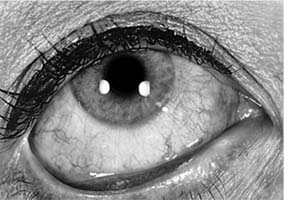

This disease is characterized by edema and hyperemia of the conjunctiva and lids (Figure 16-1) and by itching, which is always present, and watering of the eyes. There is often an associated itching sensation in the nose as well as rhinorrhea. The conjunctiva appears pale and boggy because of the intense edema, which is often rapid in onset. There is a distinct seasonal incidence, some patients being able to establish the onset of their symptoms at precisely the same time each year. These times usually correspond to the release of pollens by specific grasses, trees, or weeds.

Figure 16-1

Figure 16-1: Hay fever conjunctivitis. Note edema and hyperemia of the conjunctiva. (Courtesy of M Allansmith and B McClellan.)